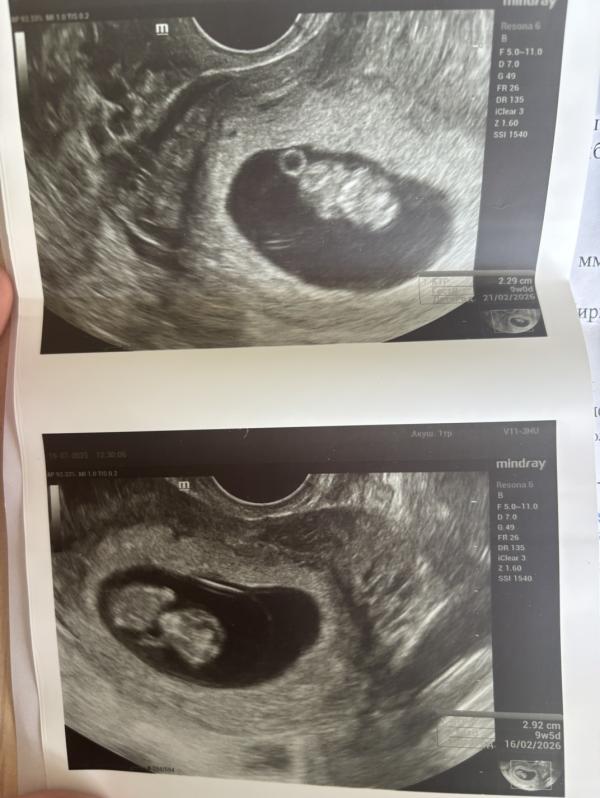

Крошечки❤️

Все с малышами хорошо,каждый живет в своем домике. В пятницу иду вставать на учет.

На фото срок 9 недель.

Эмбрионы в пя увидели в 6,6